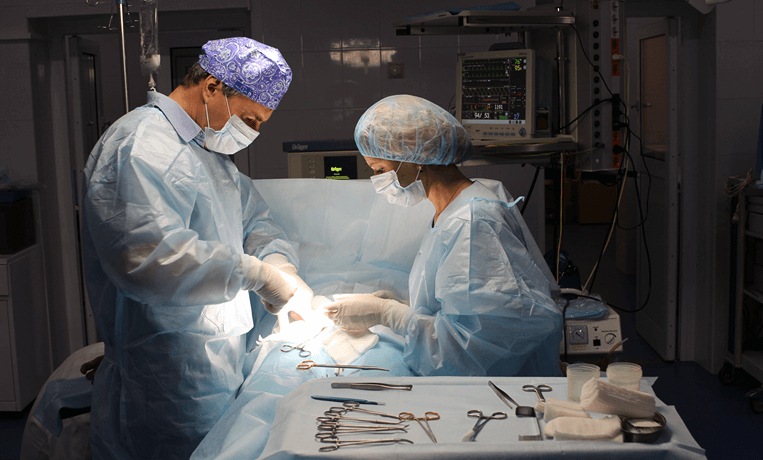

- Комбинированная флебэктомия

- Минифлебэктомия

- Флебэктомия вен нижних конечностей

- Хирургия